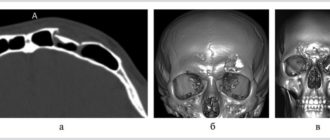

Перелом в области околоносовых пазух со смещением фрагментов костной и хрящевой ткани — Без